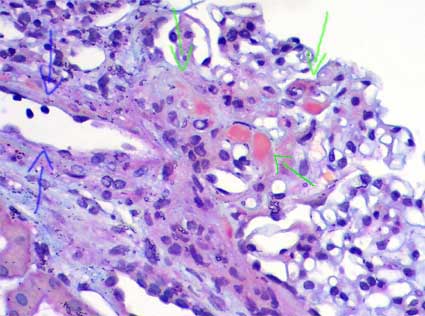

FSGS perihilar variant

Defining criteria include both of the following: a) there must be at least 1 glomerulus with perihilar hyalinosis, with or without sclerosis; and b) more than 50% of glomeruli with segmental lesions must have perihilar sclerosis and/or hyalinosis.

Other glomeruli may show lesions as described in FSGS NOS. In some cases there is some degree of mesangial proliferation, and lipid vacuoles and hypertrophy or hyperplasia of podocytes may be identified, although this last finding is less frequent than in other variants.

This type of lesion is common in patients with secondary forms of FSGS mediated by an adaptive response to nephron loss or glomerular hypertension: in association with obesity, cyanotic congenital heart disease, reflux nephropathy, renal agenesis, or any renal disease with reduced number of functioning nephrons.

Figure 8. In this microphotography, we see a glomerular arteriole (blue arrows), in the tuft there are hyaline segments in its vascular pole (green arrows). The perihilar variant characterize by al least one glomerulus with perihilar hyalinosis (as seen in this image), accompanied or not by sclerosis, and more than 50% of glomeruli with segmental lesions must have sclerosis and/or perihilar hyalinosis. There must not be glomeruli with collapsing or hypercellular lesions. (Mason’s trichrome, X400).